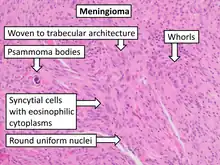

- A woven architectural pattern

- Psammoma bodies (spheroid calcifications)

- Syncytial cells (having indistinct cell membranes) with eosinophilic (pink) cytoplasms

- Round uniform nuclei

- Whorls (concentric cell arrangements)[15]

Histologically, meningioma cells are relatively uniform, with a tendency to encircle one another, forming whorls and psammoma bodies (laminated calcific concretions).[18] As such, they also have a tendency to calcify and are highly vascularized.